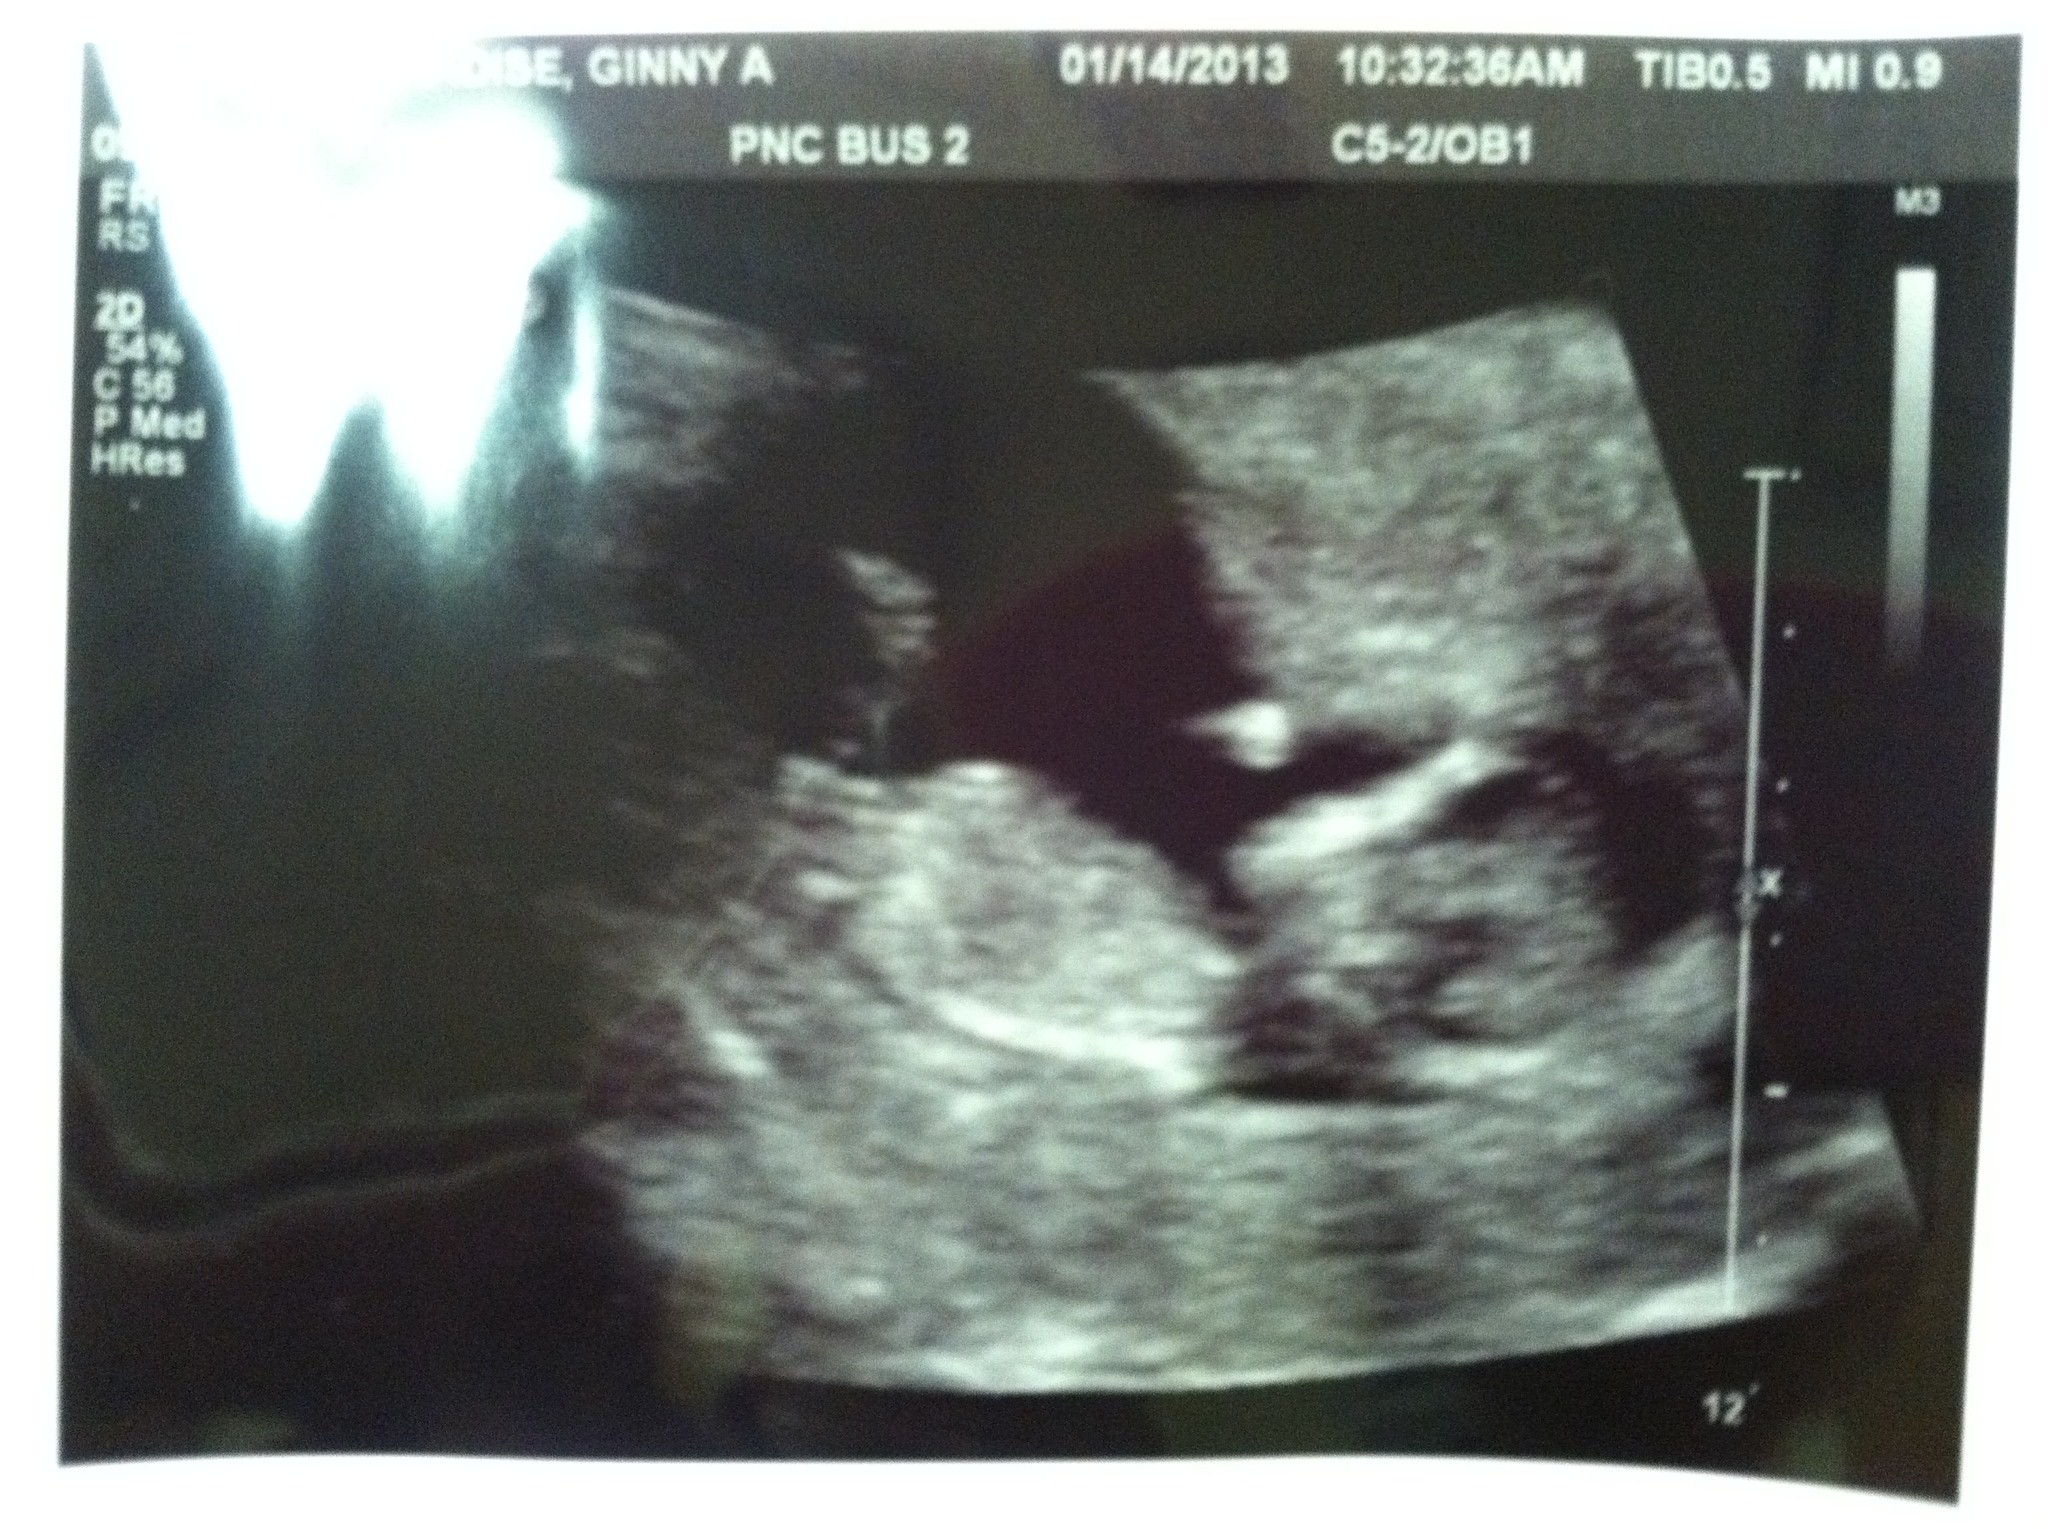

For a GIRL: When baby is in supine (laying on back position) the curve of the spine is lower, the coccyx (tailbone) almost touches the floor of the uterus.

For a BOY: In supine position the curve of the tailbone kicks up higher more 30-45degrees higher from the floor.